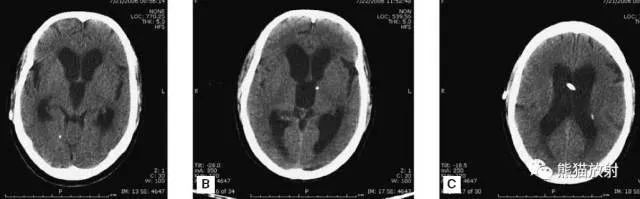

▲动脉瘤破裂导致蛛网膜下腔出血、

脑室积血、非交通性脑积水

与外伤性蛛网膜下腔出血不同,动脉瘤破裂导致的SAH常不累及大脑凸面,而位于基底池附近。脑动脉瘤常位于鞍上池的Willis环血管。

A:四脑室积血;

B:中脑导水管、环池、右侧侧脑室颞角积血,前交通动脉处(动脉瘤好发位置)出血密度较高;

C:三脑室积血;

D-F:侧脑室积血,蛛网膜下腔出血(血液代替了脑脊液)。